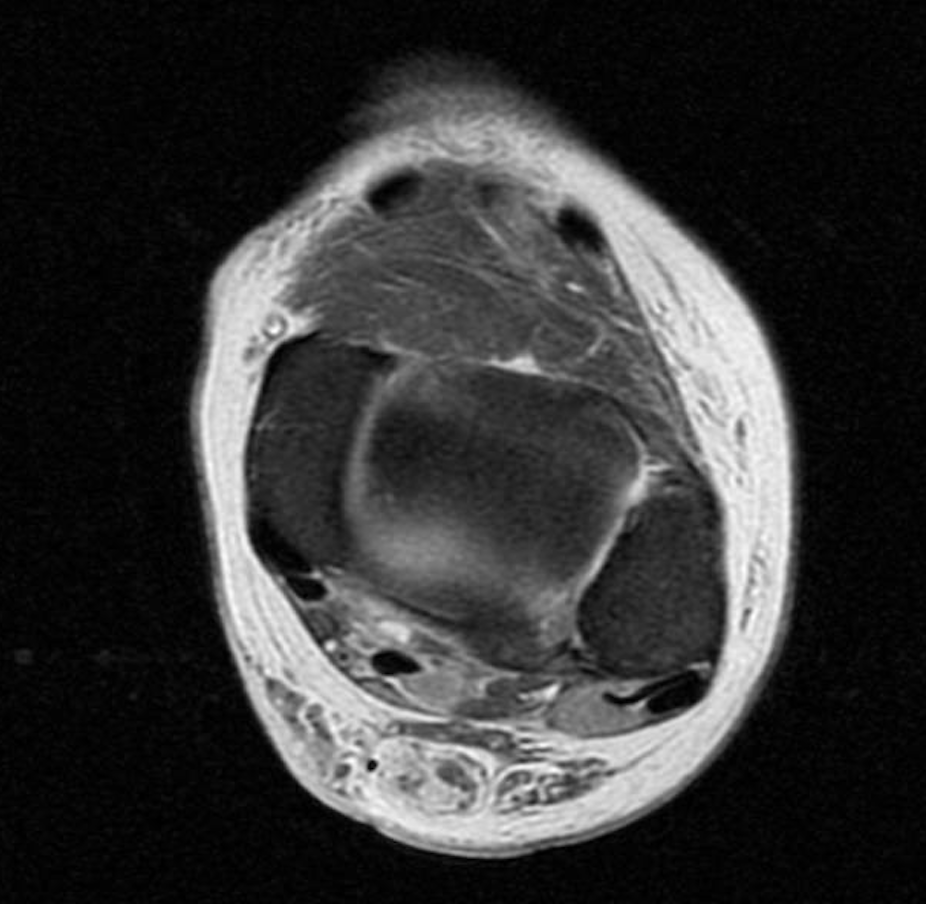

A physical exam revealed edema bilateral to the lower extremities with ecchymosis on the left side but not on the right lower extremity. The patient was neurovascularly intact, and the exam revealed a positive Thompson test on the bilateral lower extremities with no active ankle plantarflexion on the left and right sides. There was a palpable delve in the Achilles on both sides. An MRI that day on both lower legs revealed bilateral Achilles tendon ruptures with a left gap of 3.5cm and a right gap of 2.5 cm.